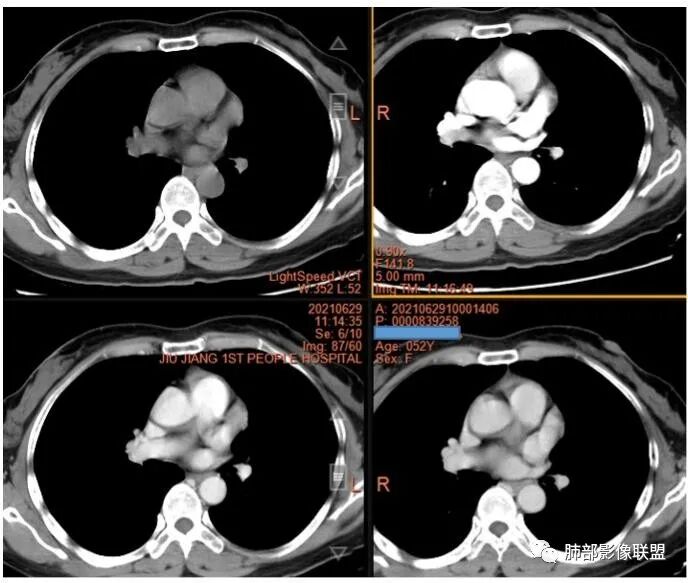

2.左上纵隔肺门夹角处孤立实性密度结节影,边界清楚浅分叶,密度均匀,未见液化、分隔及钙化。

3.动脉期起显著强化并延续至静脉期,强化程度均低于同期胸主动脉。病灶弧形推压左上肺动脉,毗邻左肺上叶支气管但未见侵蚀及突入,相应支气管未见狭窄。

4.胸腺瘤多少出乎预料,背井离乡,且强化程度如此夸张。

但本例提示我们,发生于前纵隔的肿块我们不能轻易抛开胸腺这一来源。